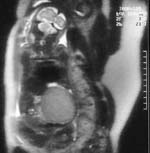

Apport de l’IRM dans le diagnostic :

Echographiquement :

- Masse solide échogène bien encapsulée

- Séparation nette avec la portion rénale normale

- Zones anéchogènes : zones d’hémorragie ou de nécrose tumorale

- Hydramnios possible voire anasarque foeto-placentaire

- Flux à basse résistance au doppler

- Rapidité de croissance évoquant le caractère malin de la tumeur